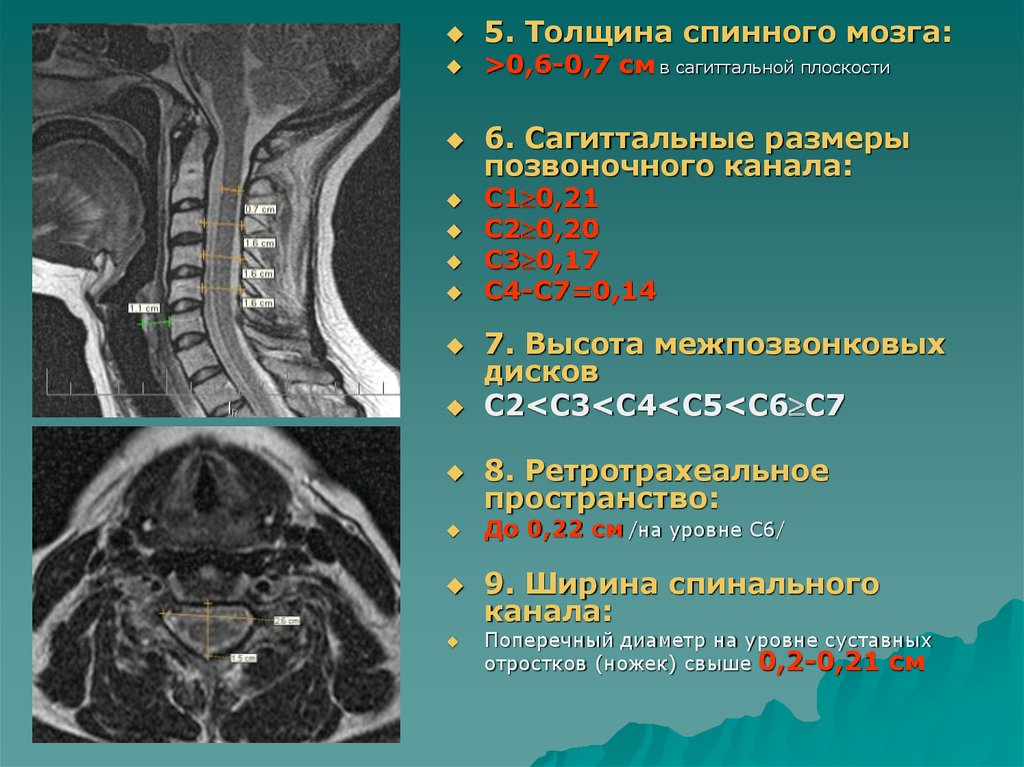

Отделы позвоночника для мрт схема фото и названия